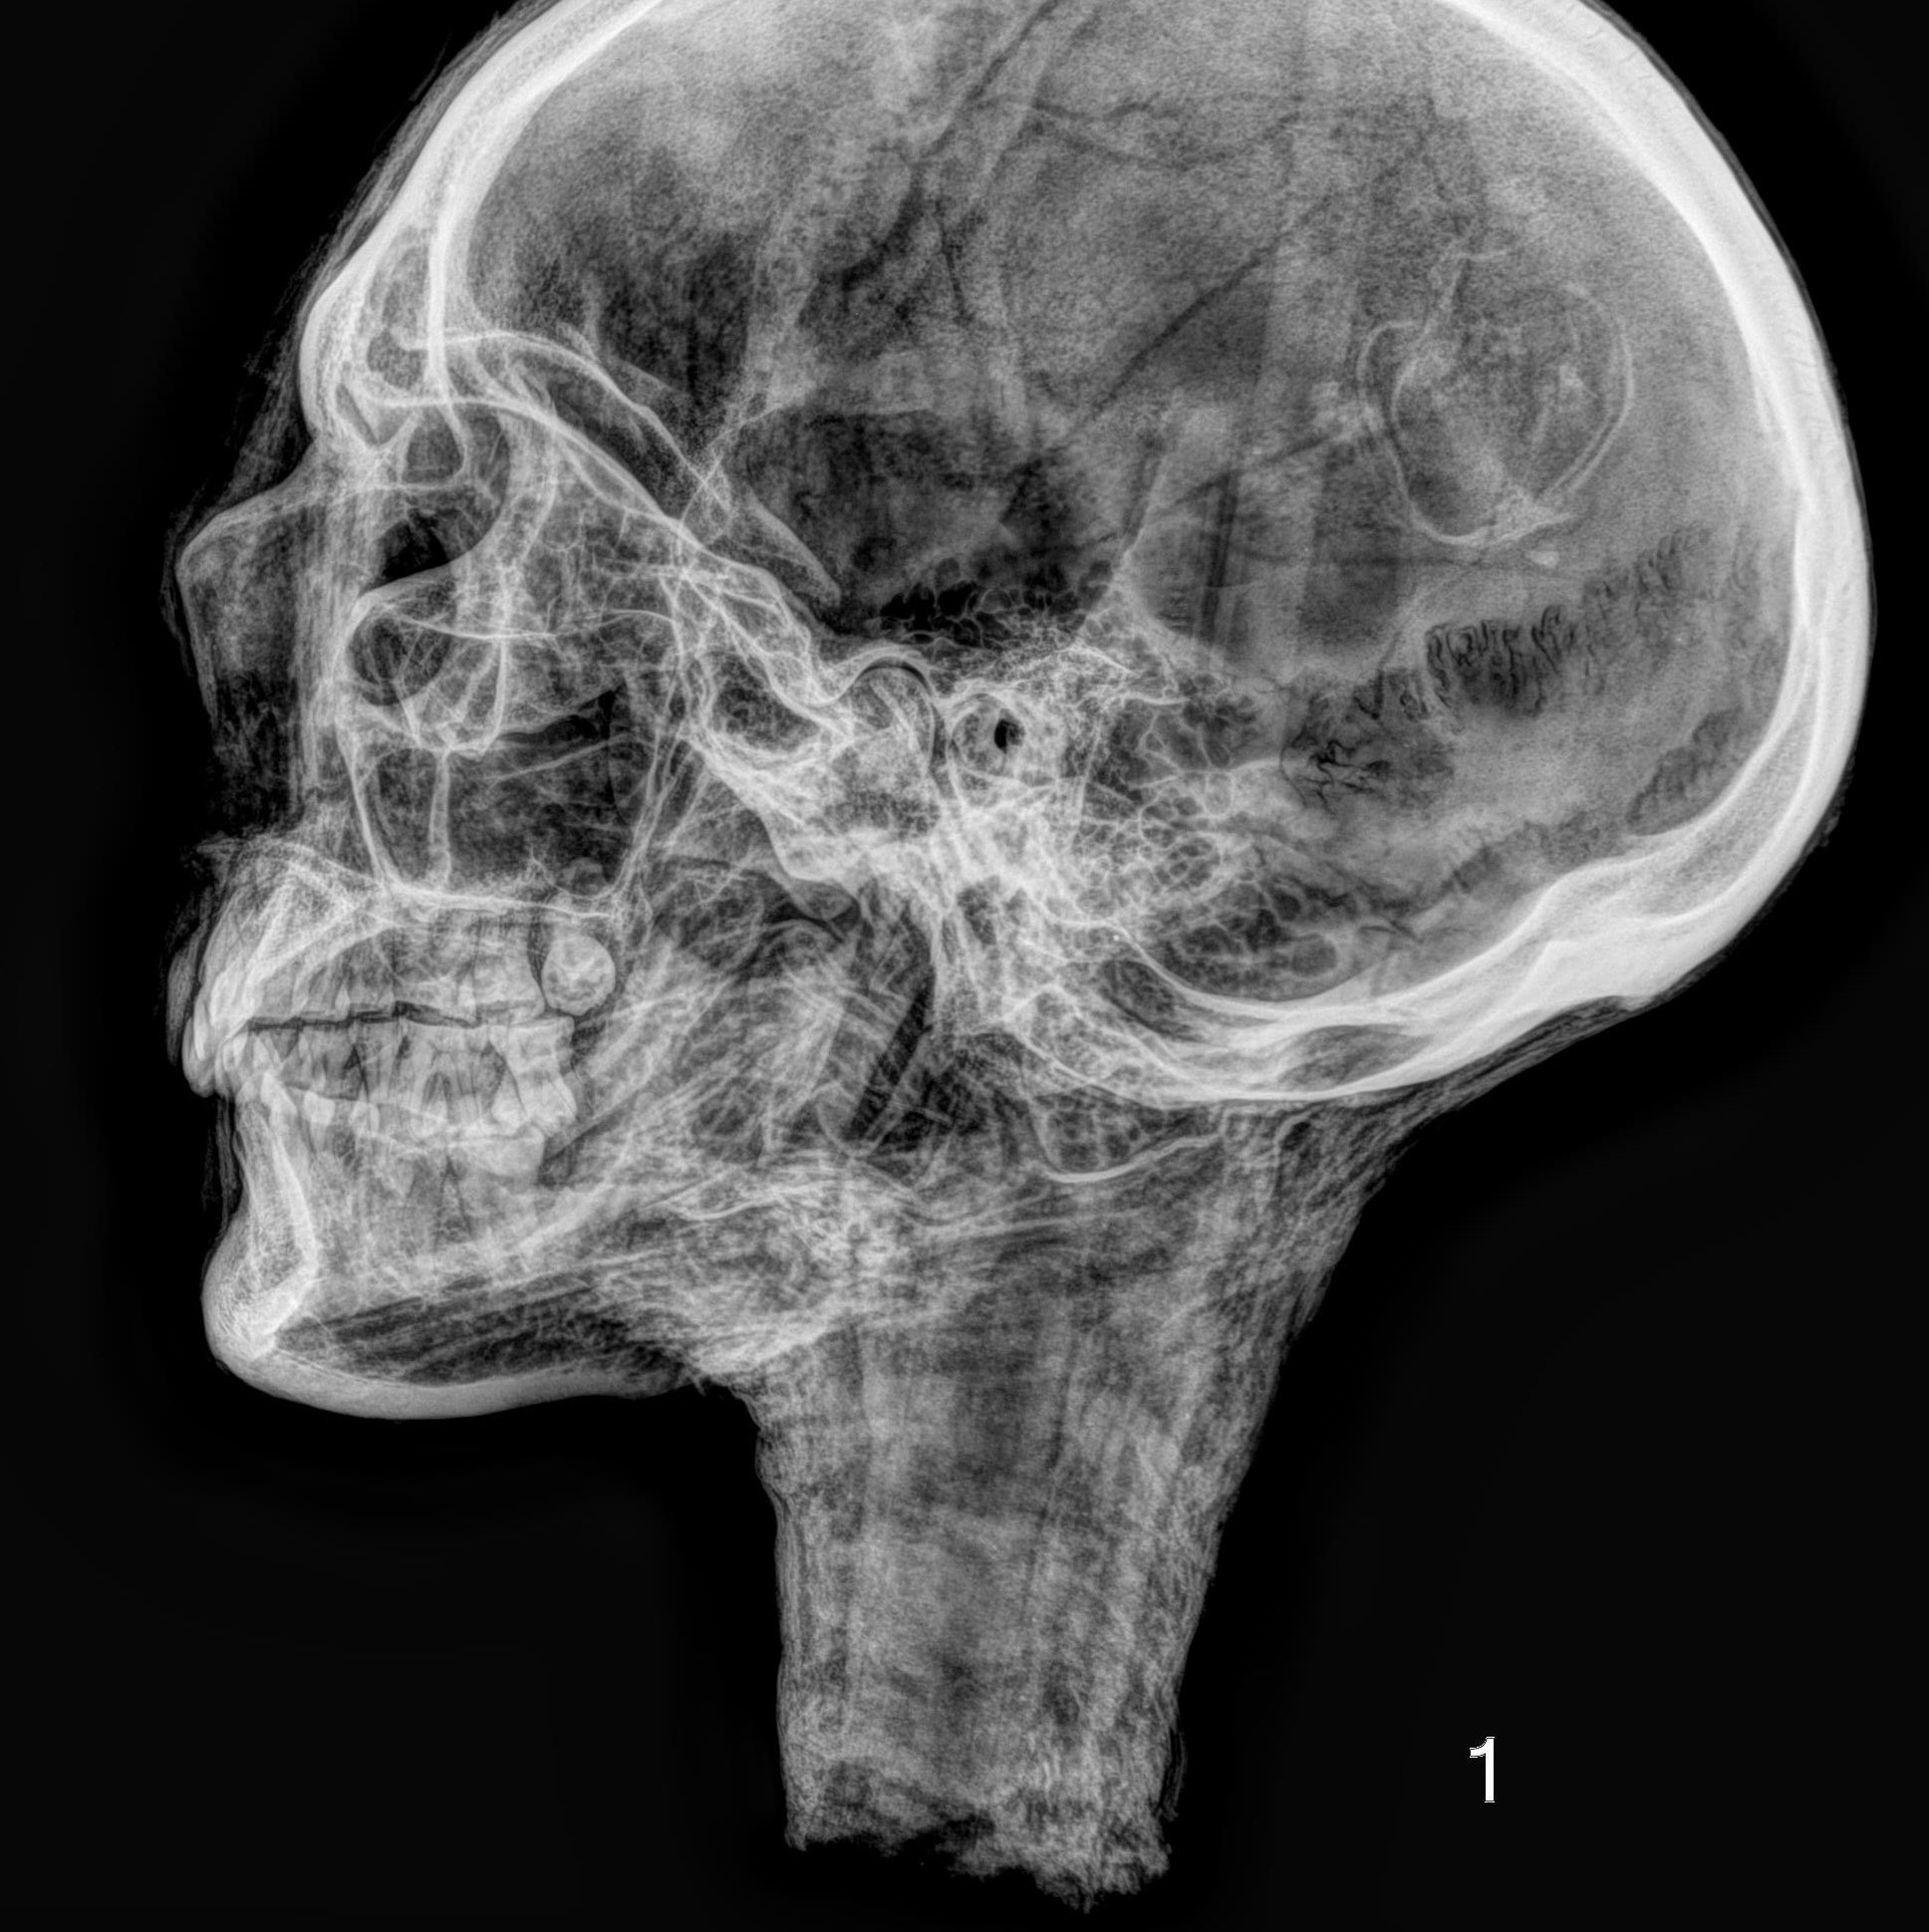

The methodology behind C14 analysis is as fascinating as the results it produces. Photographic images, X-ray images for analyzing internal structures and the graphical evaluation of C14 dating results offer in-depth insights into the condition and history of the examined individual. With cutting-edge techniques such as the Single Stage Accelerator Mass Spectrometer (SSAMS) and the Automated Graphitization Equipment AGE-3, even the smallest details can be deciphered.